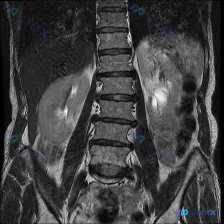

整理到一份腹部MRI冠状位T2加权图像的资料,附带提了一句“脊柱侧弯”,但实际看下来核心发现完全在肾脏上。

先把影像里的关键信息列一下:

- 肝脏、脾脏、右肾看起来还好;

- 左肾基本被一个大范围的病变占了,正常皮髓质结构不清,边缘也不太规则;

- T2信号很杂,有明显的极高信号区(可能是液体、坏死或囊性变),也夹着中等信号的实性成分;

- 目前这张图没看到明显的肾门大血管侵犯,也没看到腹主动脉旁成团肿大淋巴结,没腹水。